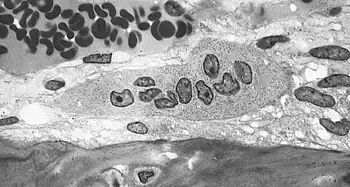

Osteoblasts actively synthesizing osteoid containing two osteocytes. -

Osteoclast, with bone below it, showing typical distinguishing characteristics: a large cell with multiple nuclei and a "foamy" cytosol.